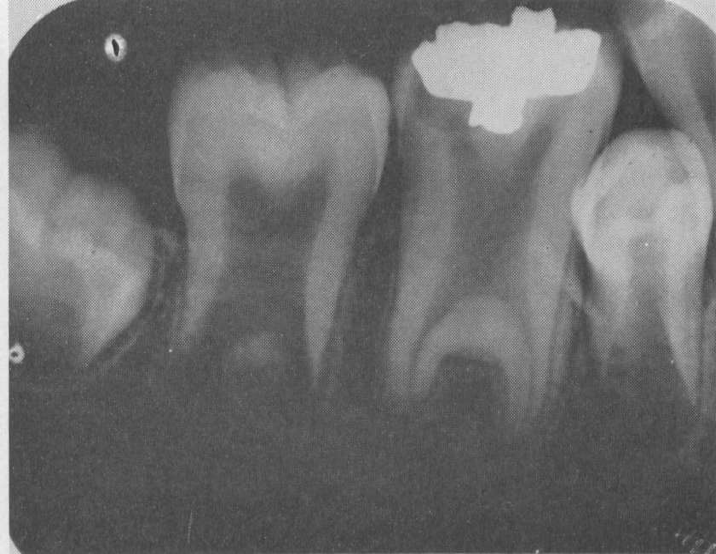

Taurodontia